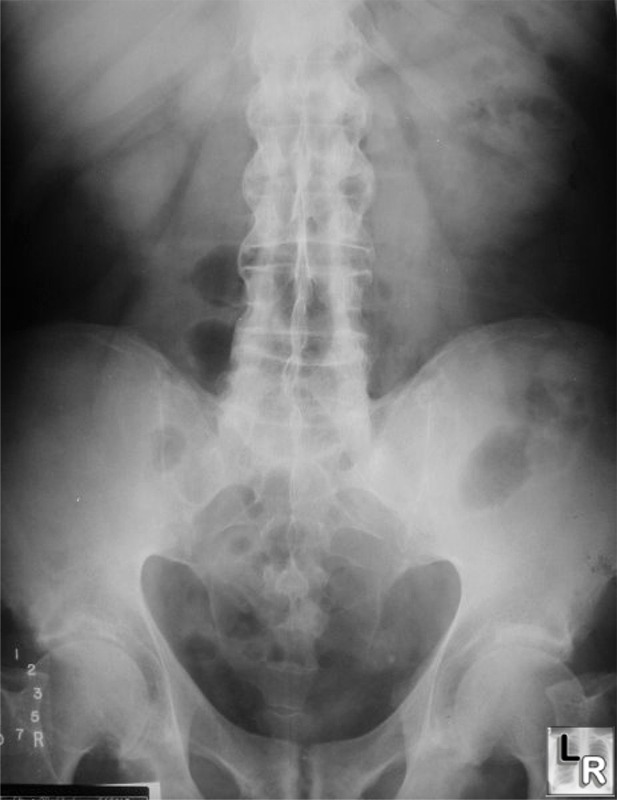

From www.wikidoc.org

Ankylosing spondylitis x ray wikidoc Ankylosing Spondylitis X Ray Si Joint Early changes of sacroiliitis (inflammation of the sacroiliac joints) are not. Dosing informationwatch videos for hcps Ankylosing spondylitis often affects the sacroiliac or si joint, which may cause pain in the lower back or buttocks. Imaging is an integral part of the management of patients with ankylosing spondylitis and axial spondyloarthritis. Typical appearance of bamboo spine with multiple syndesmophytes between. Ankylosing Spondylitis X Ray Si Joint.